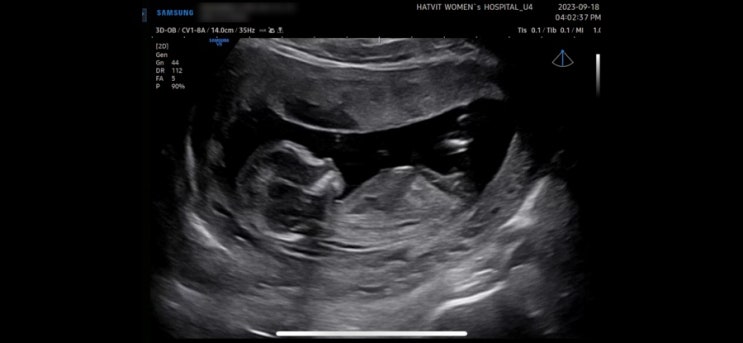

[임신 13주차] 1차 기형아 검사/정밀초음파 입체초음파/인터그레이티드 검사/태몽

안녕하세요. 임신 13주차가 된 르네체리 ? 입니다. 임신 12-13주차가 된 산모라면 떨리는 기형아 검사를...